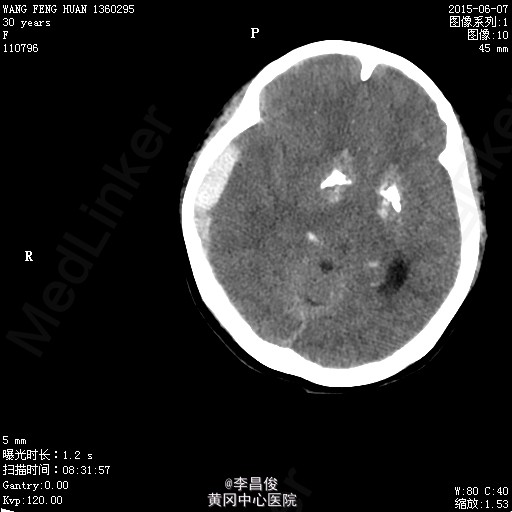

入院完善相关检查:血常规:血红蛋白 105.1g/L,血小板 95*10^9/L,尿常规:蛋白 -,肝功能:谷丙转氨酶 77.9U/L,尿酸 426.7umol/L,凝血机制:D-二聚体 2267ng/ml。 血脂:甘油三酯:3.31;低密度脂蛋白:5.46,甲功、心肌三项、心脏彩超正常, 给予对症处理,患者于6月4 日8:42分在会阴左侧切下以LOA位顺利娩出一活女婴,产程顺利,产时血压最高达160/110mmHg,给予心痛定一粒舌下含服,产后回病房后监测血压在100-140/70-90mmHg之间波动。6月7日5点多头痛明显,急查头部CT提示:右侧额颞顶部硬模下血肿。请神经外科急会诊,建议转专科治疗。转外科后,患者意识障碍加重,6月8日17:30时急诊全麻下行“右侧开颅硬膜下血肿清除+去骨瓣减压术”,术后转重症医学科。稳定后拔除气管插管后转回专科,行抗感染、止血、神经营养、脱水治疗,定期换药及CT复查,后出现癫痫发作,给予抗癫痫治疗。6月13日患者癫痫发作后呈持续状态,药物控制不理想,故转入ICU进一步监护治疗。患者神志昏迷,给予持续泵入丙戊酸钠、咪达唑仑控制抽搐,适当脱水、抗感染、营养支持及对症处理,并及时复查相关检查。患者癫痫控制后于17/6日顺利拔除气管导管。于17/6日再次癫痫发作1次,很快缓解。转神经科继续治疗:患者神志清楚,精神、食欲一般,诉左侧肢体无力伴麻木,无抽搐发作,右侧肢体肌力尚可,左侧肢体肌力3级。肌张力不高。继续给予抗癫痫、适当抗感染、肢体康复训练及对症支持治疗,一周后行颅脑MRI:未见明显异常;查体:心肺听诊(-),腹软,压痛反跳痛,双下肢无水肿,右侧肢体肌力尚可,左侧肢体肌力5级-,病理征(-),给予办理出院。

患者产前产后血压基本维持在正常水平,尿蛋白阴性,癫痫可能与额颞部出血相关性大,双侧基底节区对称行钙化有可能是Fahr综合征,为遗传性疾病,家族是否有类似病例?